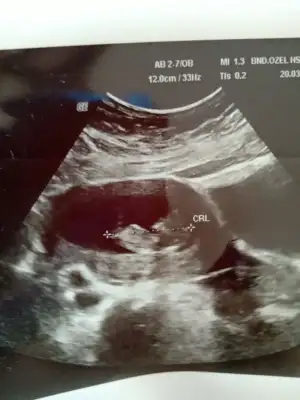

Net değil 12 13 haftada paylaşın sanki eminde değilim erkek gibi gibi![]()

Dr +getirmiş sanki erkek gibi gibi siz 12 13 hafta usg de paylaşın emin olamadım

Erkek gibiBuda diğer pozu o gün ki ölçüm olmayan ters duruyordu bunda ondan çevirip çektim resmini bunda da belli olmazsa 12 gün sonra kontrolümüz var o zaman atarım 14 haftalık olacak kısmetse o zaman ❤Ikra meyra cvp için teşekkür ederim ❤ diğer konuya da 6 haftalık halini atmıştım ama görmemiş tiniz sizin tahminleriniz genel olarak tutuyor ❤

Teşekkür ederim ben sizin sandım herkes siiz etiketleyinceRc ederim diger taraf benim konum degil ama orası aktifde değil arada etiket yapanlar var onlara cvp veriyorumbuna göre kız ama tutmayabilir kese konumu en iyi nub 11 12 13 haftalar olmalı